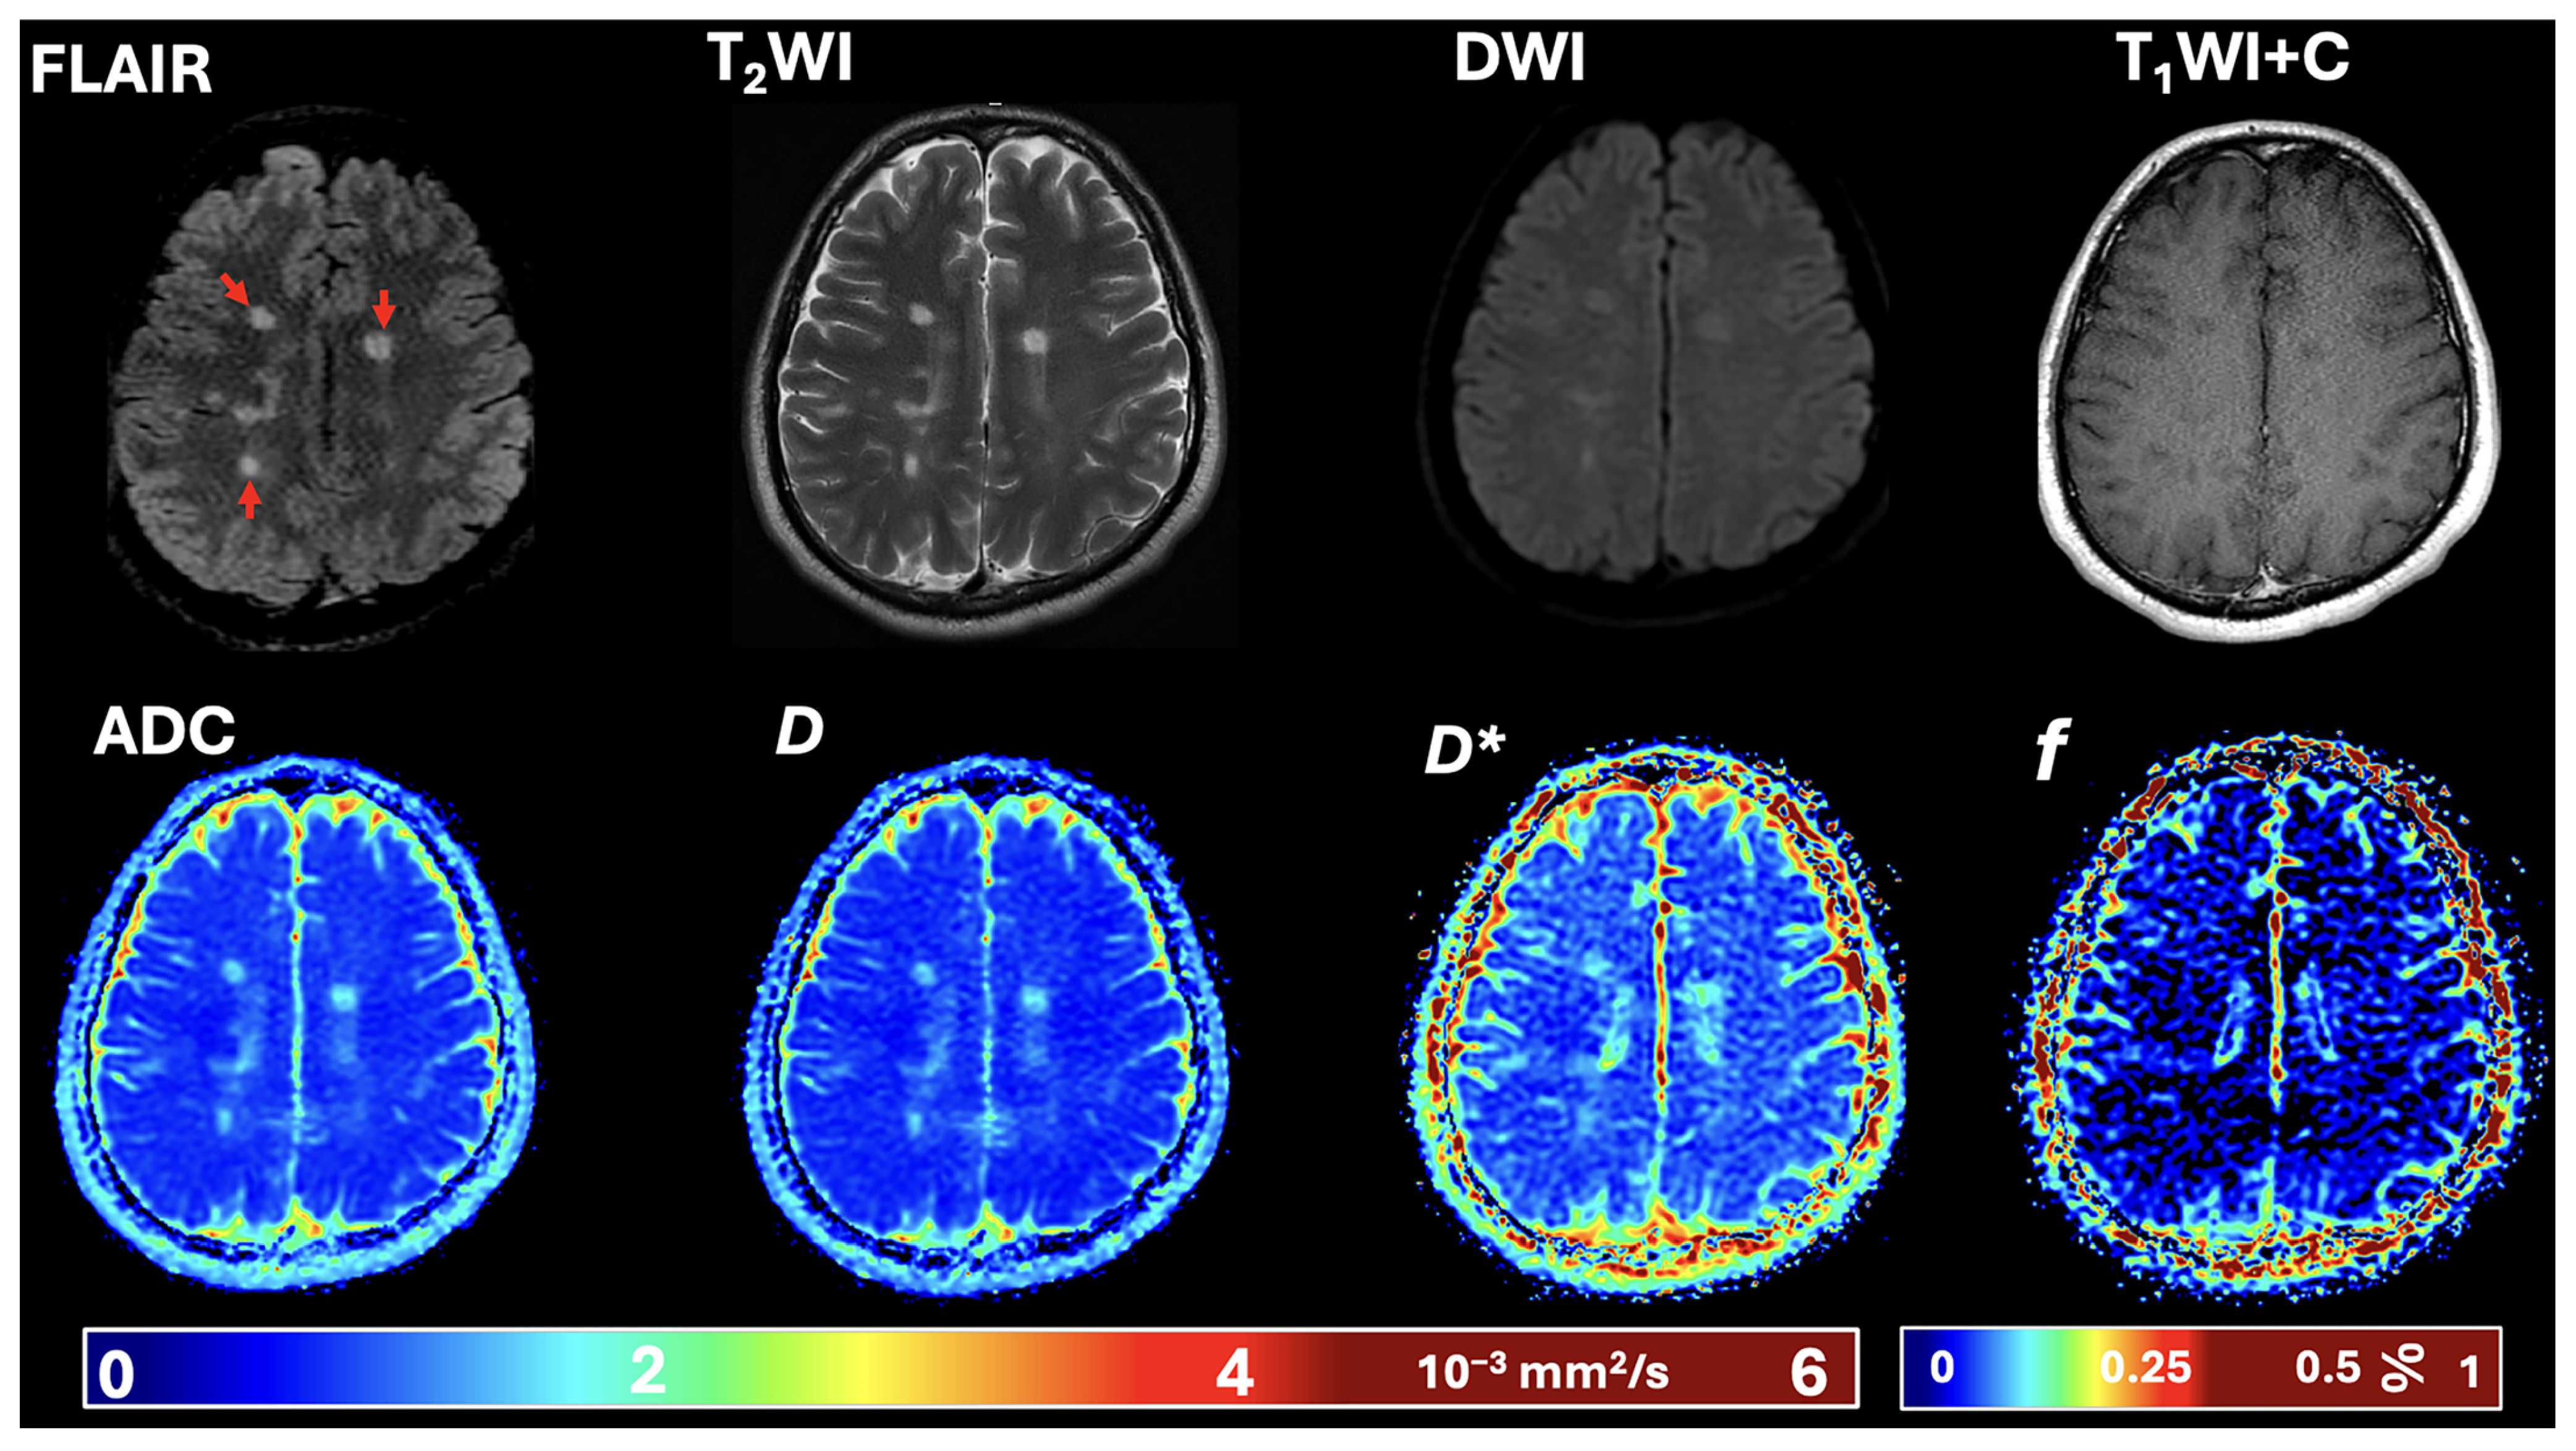

| DWI | Diffusion-weighted imaging |

| ADC | Apparent diffusion coefficient |

| D | Pure molecular diffusion |

| D* | Pseudo-diffusion |

| FLAIR | Fluid-attenuated inversion recovery |